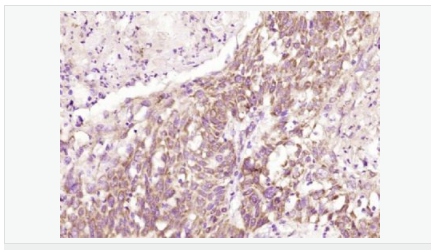

產(chǎn)品應用WB=1:500-2000 ELISA=1:5000-10000 IHC-P=1:100-500 IHC-F=1:100-500 ICC=1:100-500 IF=1:100-500 (石蠟切片需做抗原修復)

免 疫 原KLH conjugated synthetic peptide derived from human TEM8:201-300/564 <Extracellular>

Detected in umbilical vein endothelial cells (at protein level). Highly expressed in tumor endothelial cells.